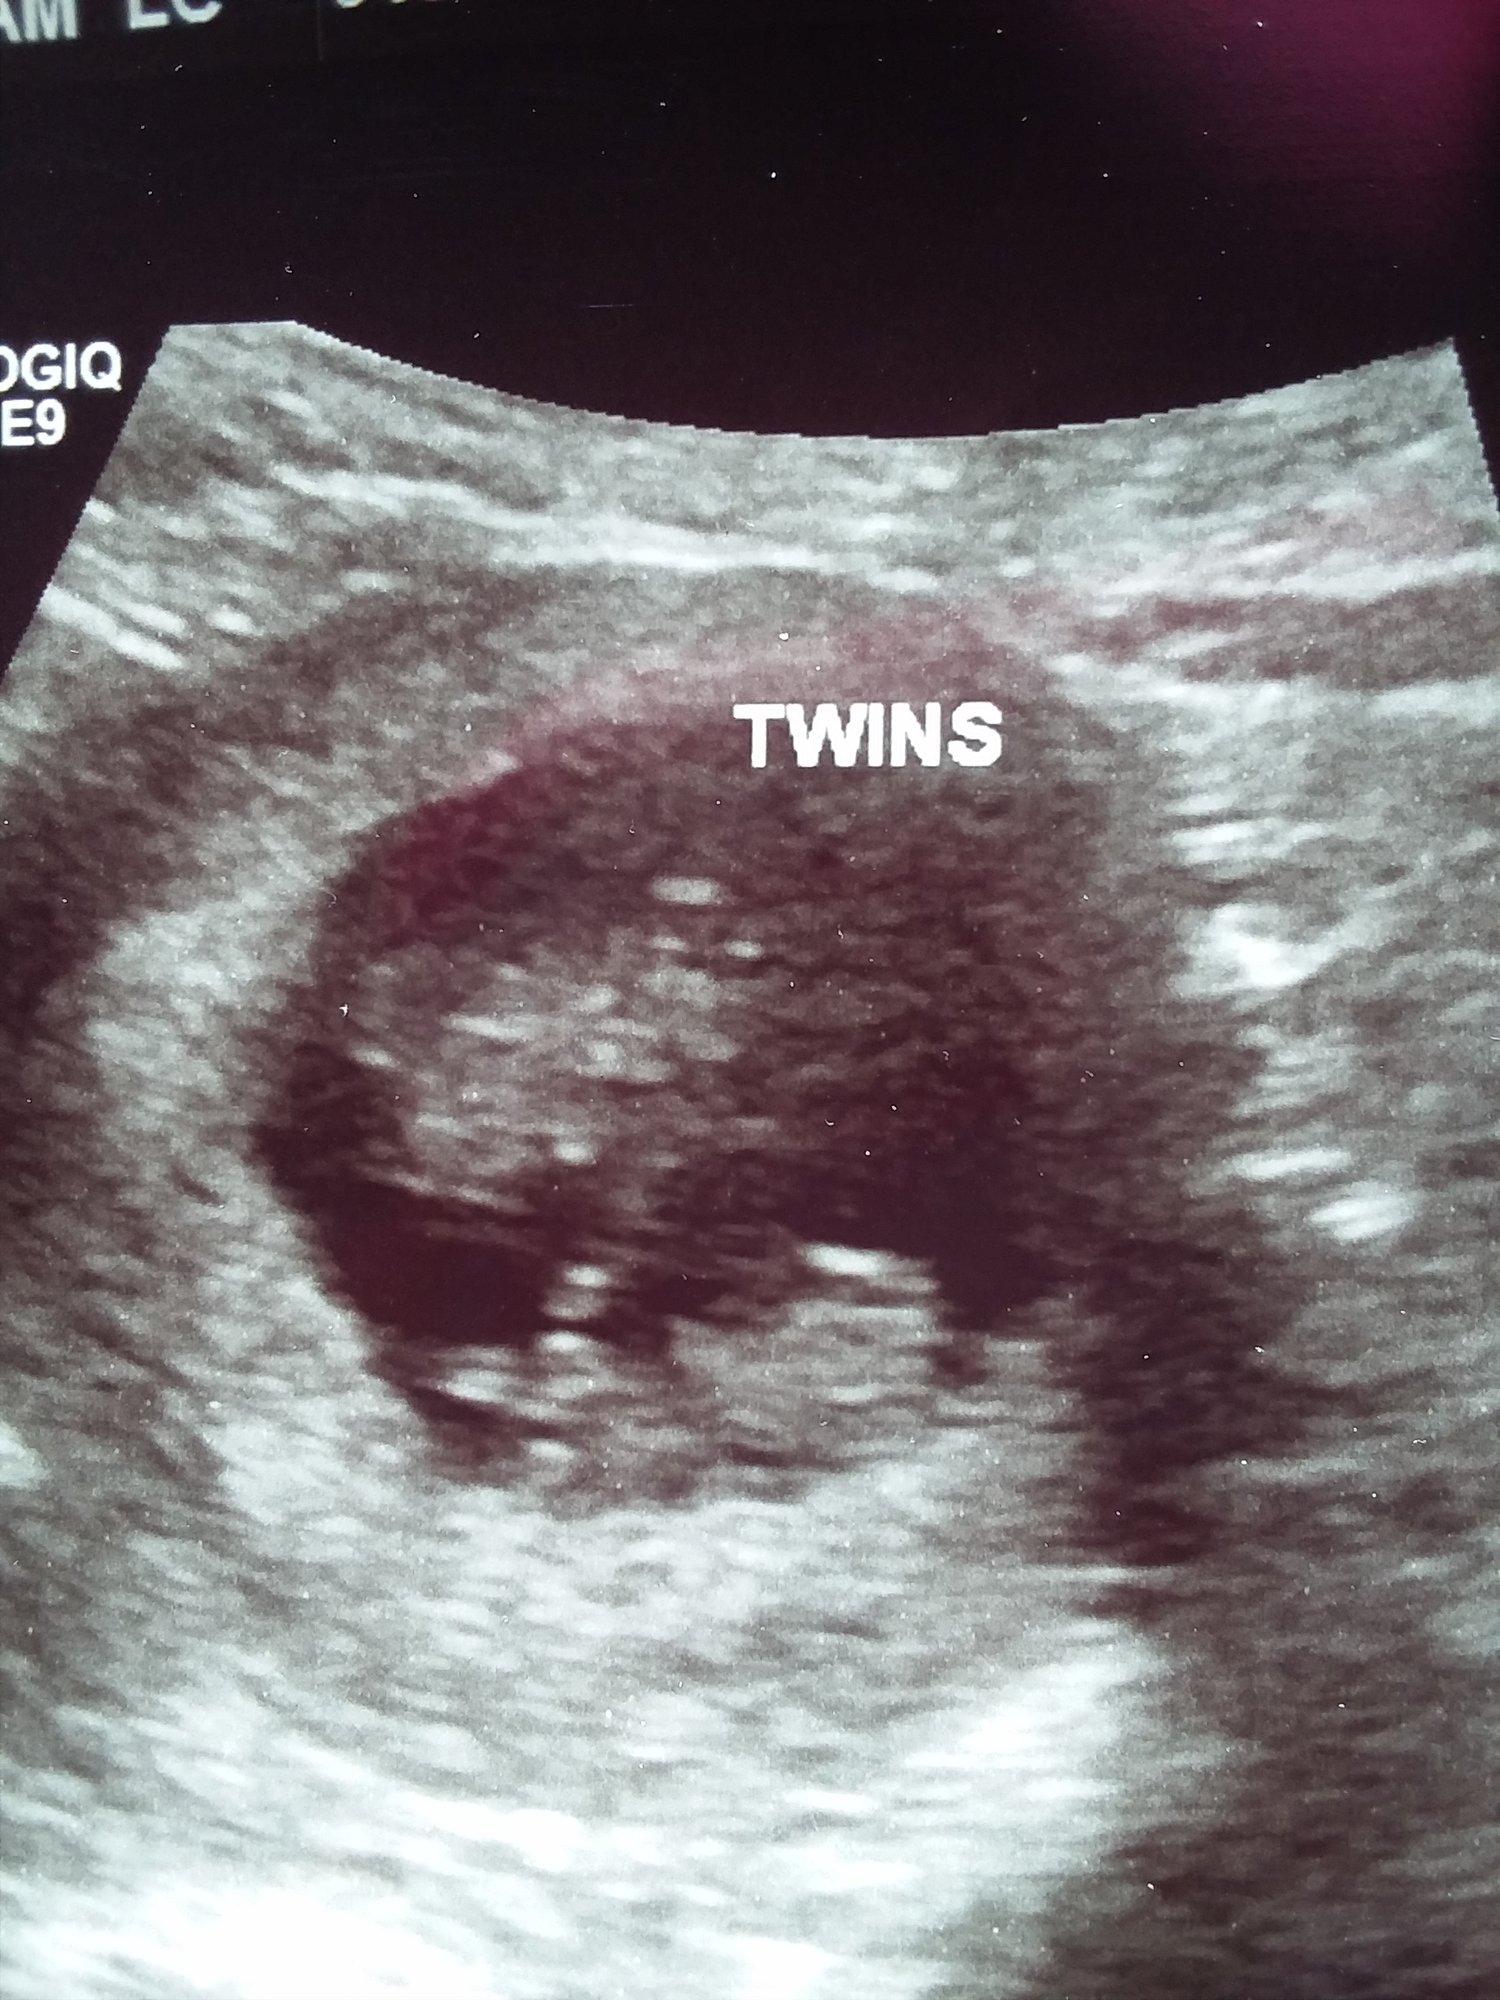

Hi everyone, 6 weeks ultrasound. I’m scheduled back for an 8 weeks ultrasound. Doctor said it’s twins but one is smaller than the other one that we had to wait and see if the other progresses. Has anyone had a similar situation? This is my 3rd pregnancy but first time twins.

• I had my first ultrasound on Monday! I'm not as far along as I thought - I thought I was past 10 weeks but I'll be just 10 weeks tomorrow. So glad I decided to have an early ultrasound - last pregnancy I just had one at 20 weeks. This time around I was having cramping and bleeding and something seemed off. I guess this is why!!!! Seeing double!! They think identical but can't quite be certain yet as I only wanted an abdominal ultrasound this visit. Needless to say I'm freaking out! New due date of November 8th instead of the 3rd...but I'm sure with twins it may be October!